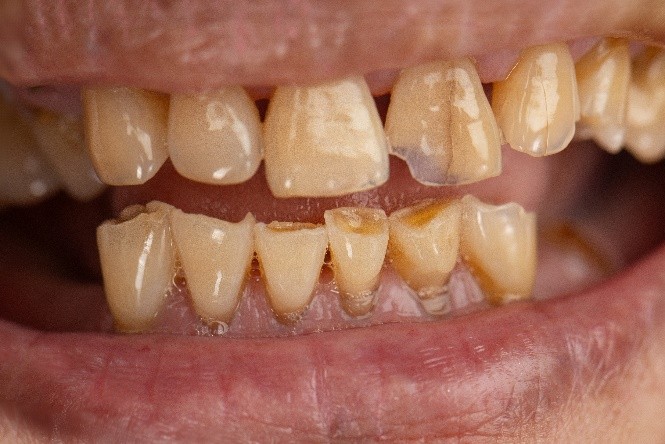

If your teeth appear shorter, flatter, or have worn-down occlusal cusps, you may already be experiencing occlusal trauma. Other warning signs include chipping or fracturing of teeth and restorative work such as fillings, veneers, or crowns. These are not merely cosmetic issues—they indicate that applied forces generated between the upper and lower dentition exceed the tolerance of tooth tissues. When these excessive forces surpass the enamel’s ability to withstand pressure, microfractures, chipping, and accelerated wear occur.

- Inadequate occlusion (bite): When the occlusion is inadequate, the teeth are unable to support and protect each other during rest or functional movements. Instead of guiding the jaw smoothly, they create restricted or abrupt contact pathways. Over time, these abnormal forces distract and damage tooth structure, leading to wear, fractures, sensitivity, and discomfort creating further harmful conditions within the system and progressive damage to the structures involved in chewing.

- Uneven tooth contacts: lead to limited and unbalanced interocclusal contact. When certain teeth touch earlier or more heavily than others, they absorb excessive forces, while other teeth fail to make proper contact with their opposing partners. As a result, these under-engaged teeth contribute very little to chewing function and cannot help distribute bite forces across the dental arches. This imbalance places disproportionate pressure on a few teeth instead of allowing all teeth to share the load evenly.

- Tight overlap: A tight or deep overlap can damage the teeth when the jaw attempts to move side-to-side or forward and back. Because the teeth cannot separate smoothly during these movements, they grind against each other instead of gliding, leading to excessive wear, fractures, and the development of cervical wedge defects. This uneven contact can also cause sensitivity to temperature changes. In addition, the chewing muscles must work much harder to disengage the teeth from these restrictive contacts, often resulting in abnormal muscle contraction, fatigue, and discomfort.

- Untreated occlusal wear progression: It creates a snowball effect—deterioration progresses more rapidly over time, leading to increasingly harmful consequences at a much faster rate. As occlusal wear progresses, the deterioration becomes continuous and increasingly difficult to control. In the more advanced stages, the process accelerates, leading to faster breakdown of tooth structure and greater functional instability.